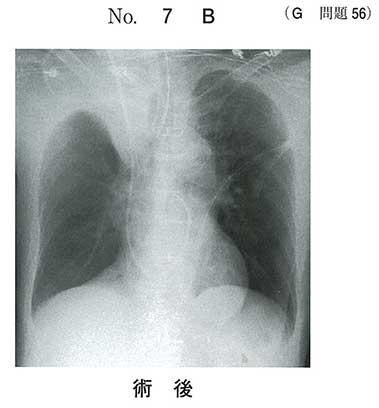

78歳の男性。冠動脈バイパス術直後で手術室に入室中である。未覚醒で人工呼吸中である。脈拍88/分、整。血圧120/80mmHg。動脈血ガス分析(吸入酸素濃度100%):pH 7.30 、PaCO2 50Torr、PaO2 200Torr、HCO3- 24mEq/L。術前と全身麻酔下手術の終了直後の胸部エックス線写真(別冊No.7A、B)を別に示す。

処置として適切なのはどれか。

a 血腫除去術

b 血栓溶解療法

c 心嚢ドレナージ

d 胸腔ドレナージ

e 気管支内視鏡による吸引